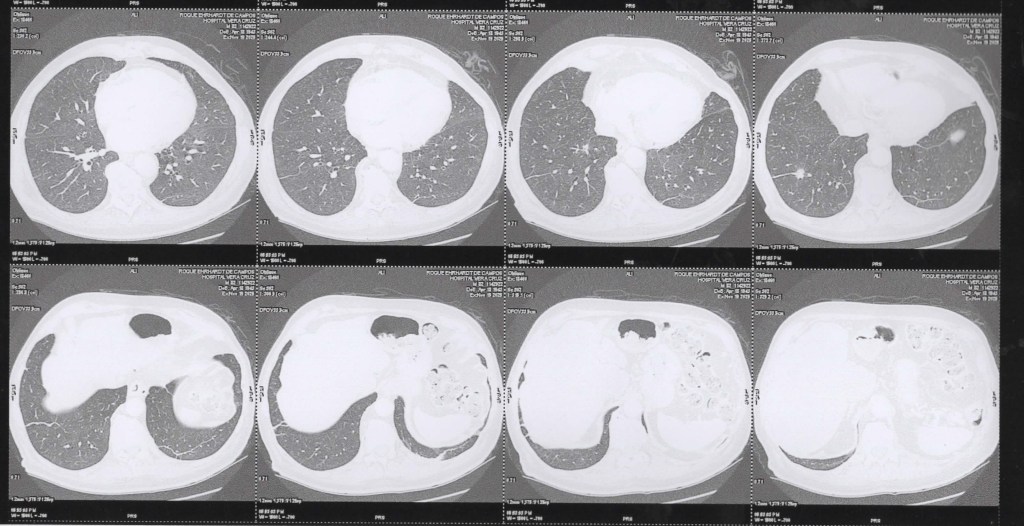

TCM Torax 19 11 2025 janela de mediastino/tecidos moles.